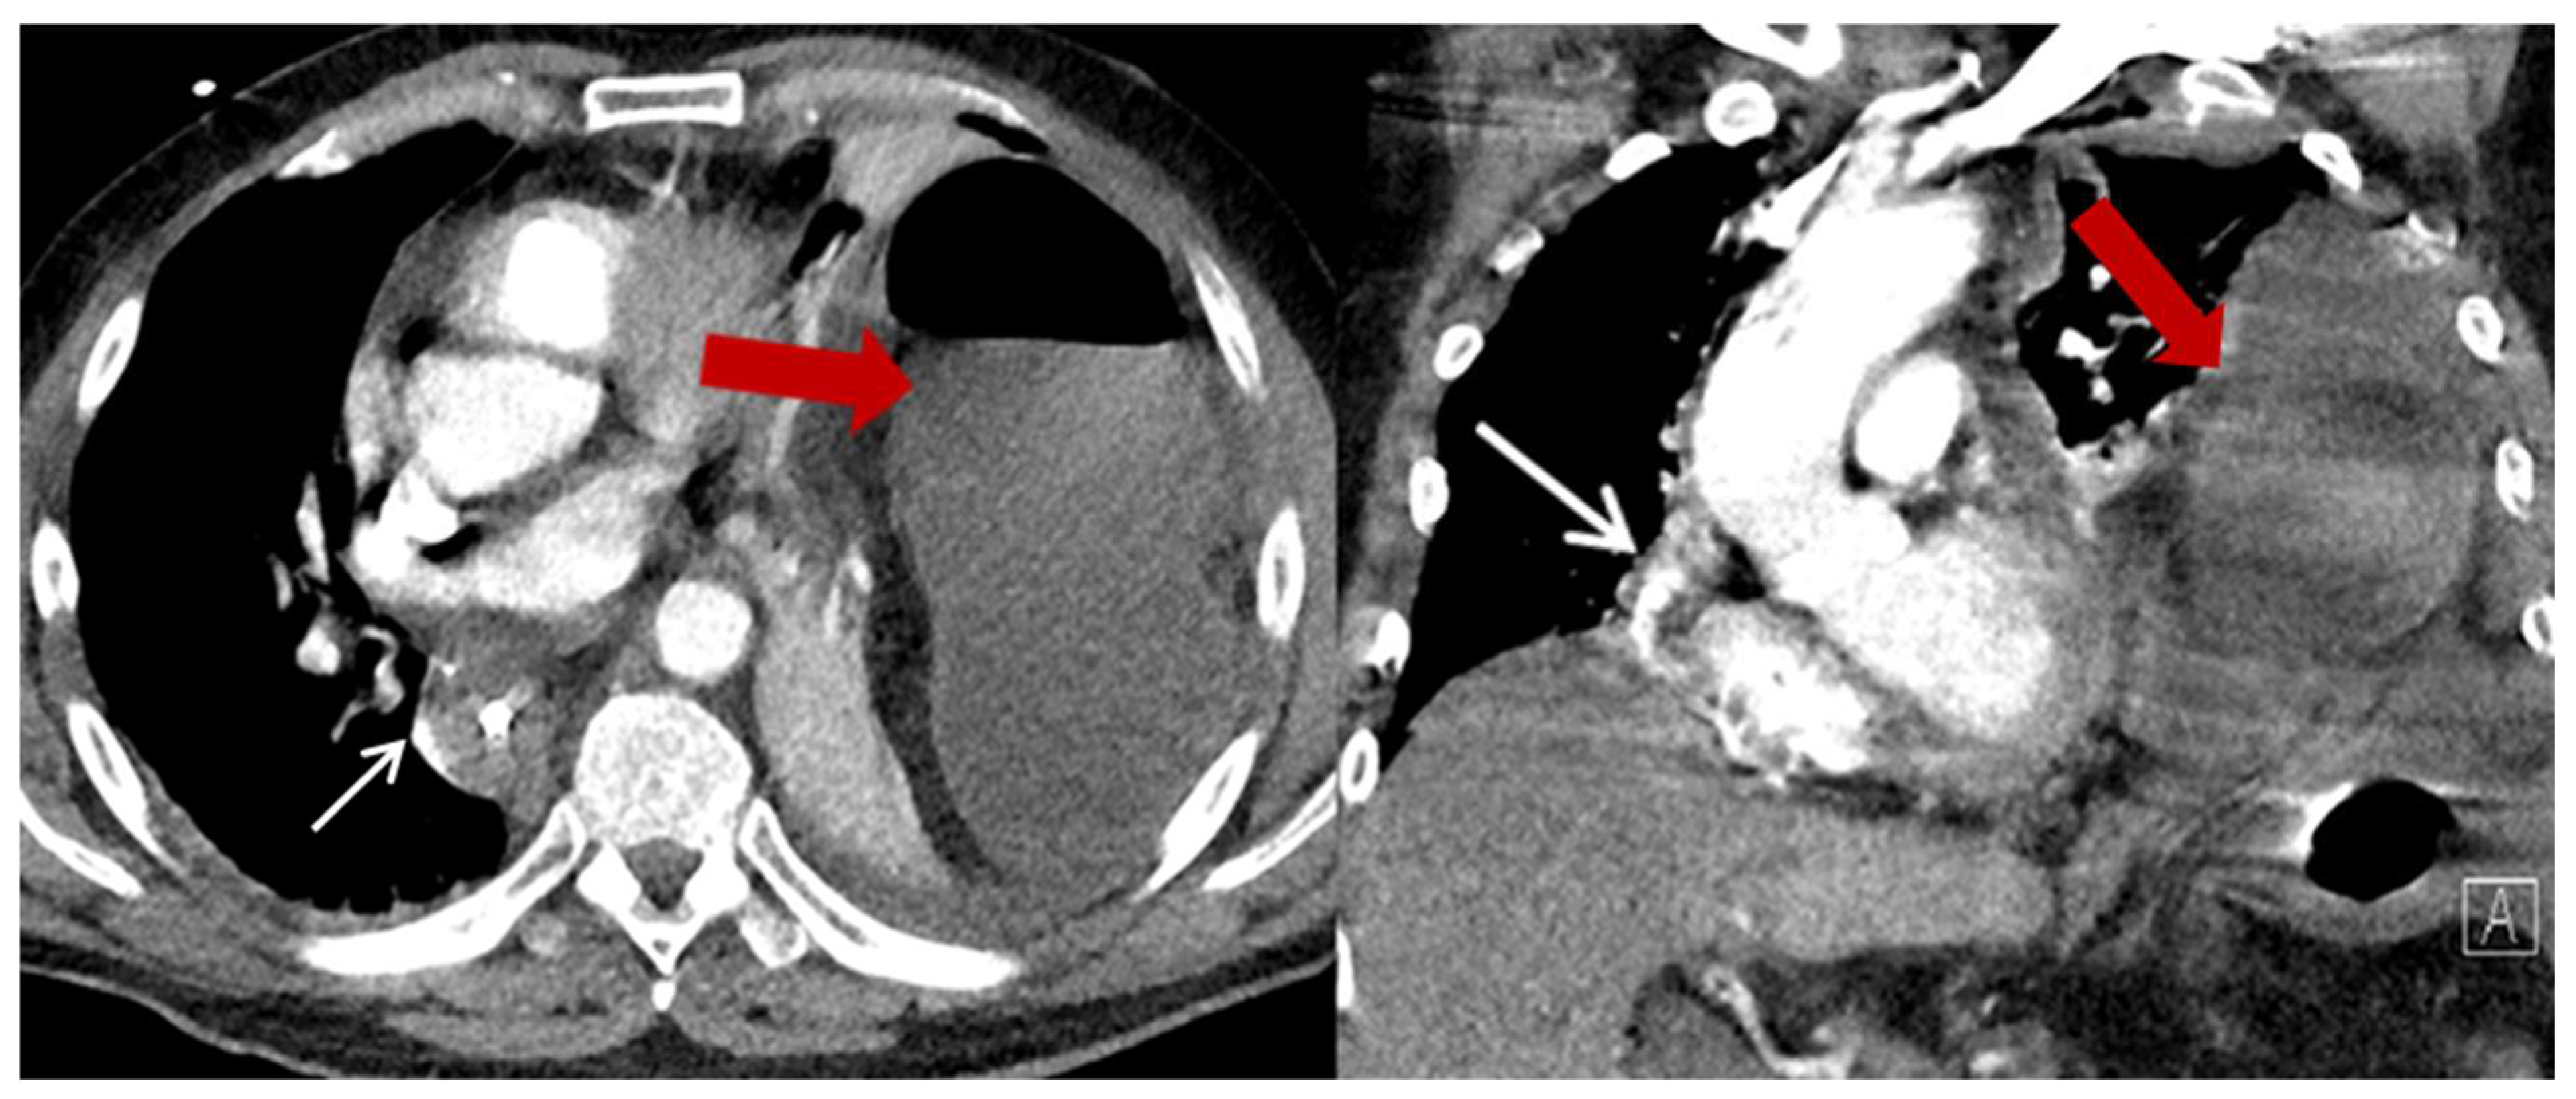

| Characteristics | HH (n = 23) (%) |

|---|---|

| Content of HH, n (%) | |

| Colon | 23 (100) |

| Additionally small bowel | 3 (13) |

| Position of the HH n (%) | |

| Left thoracic side | 18 (78.3) |

| Right thoracic side | 1 (4.4) |

| Both sides | 1 (4.4) |

| Lower mediastinum | 3 (13) |

| Symptoms n (%) | |

| None | 13 (56.5) |

| Abdominal pain and discomfort | 10 (43.5) |

| Ileus/incarceration | 4 (17.4) |